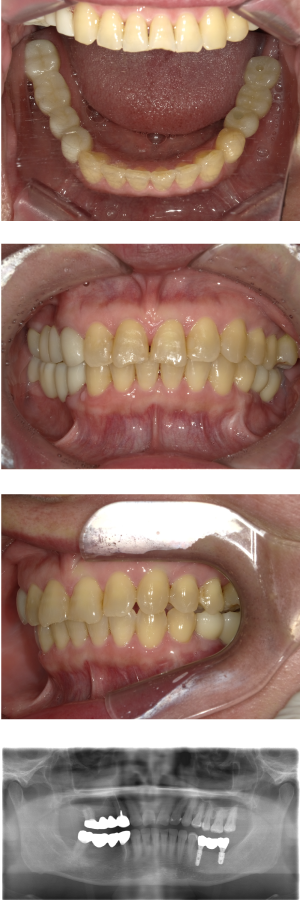

インプラント治療(左上5ソケット・GBR 右上2左上13GBR)

| 主訴 | 入れ歯だと咬めなくてつらい。 |

| 部位 | 上顎②1①2③4⑤Br |

| 治療期間 | 約9ヶ月 |

| 費用 | ¥1,794,100(税込) |